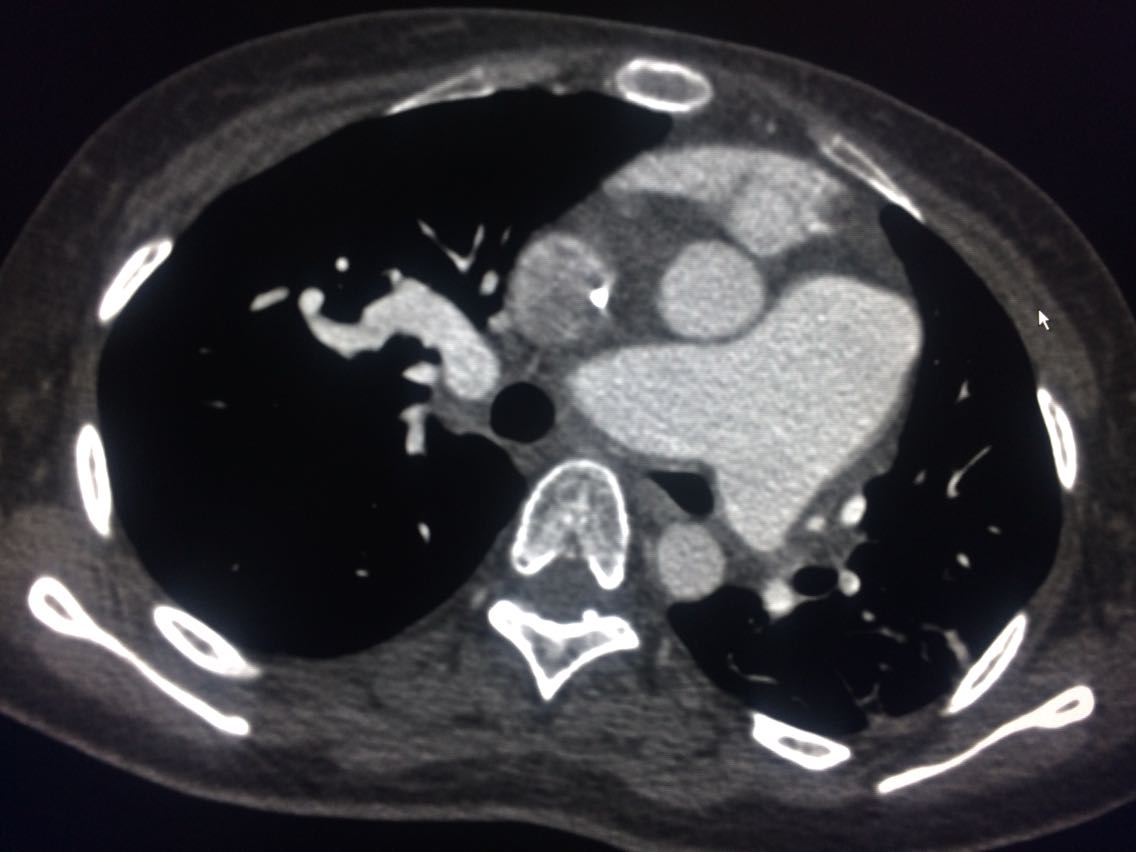

诊断,肺动脉高压。 鉴别诊断,肺动脉栓塞。 影像诊断,肺动脉高压,肺门区出现残根征,肺动脉扩张,肺动脉段膨隆,心影增大。CTA见迂曲增宽的肺动脉。 肺栓塞,影像可见典型充型缺损影,伴随肺纹理的减少。 治疗以对症处理为主,病人病史14年。 讨论诊断和鉴别诊断? 随访,症状好转。